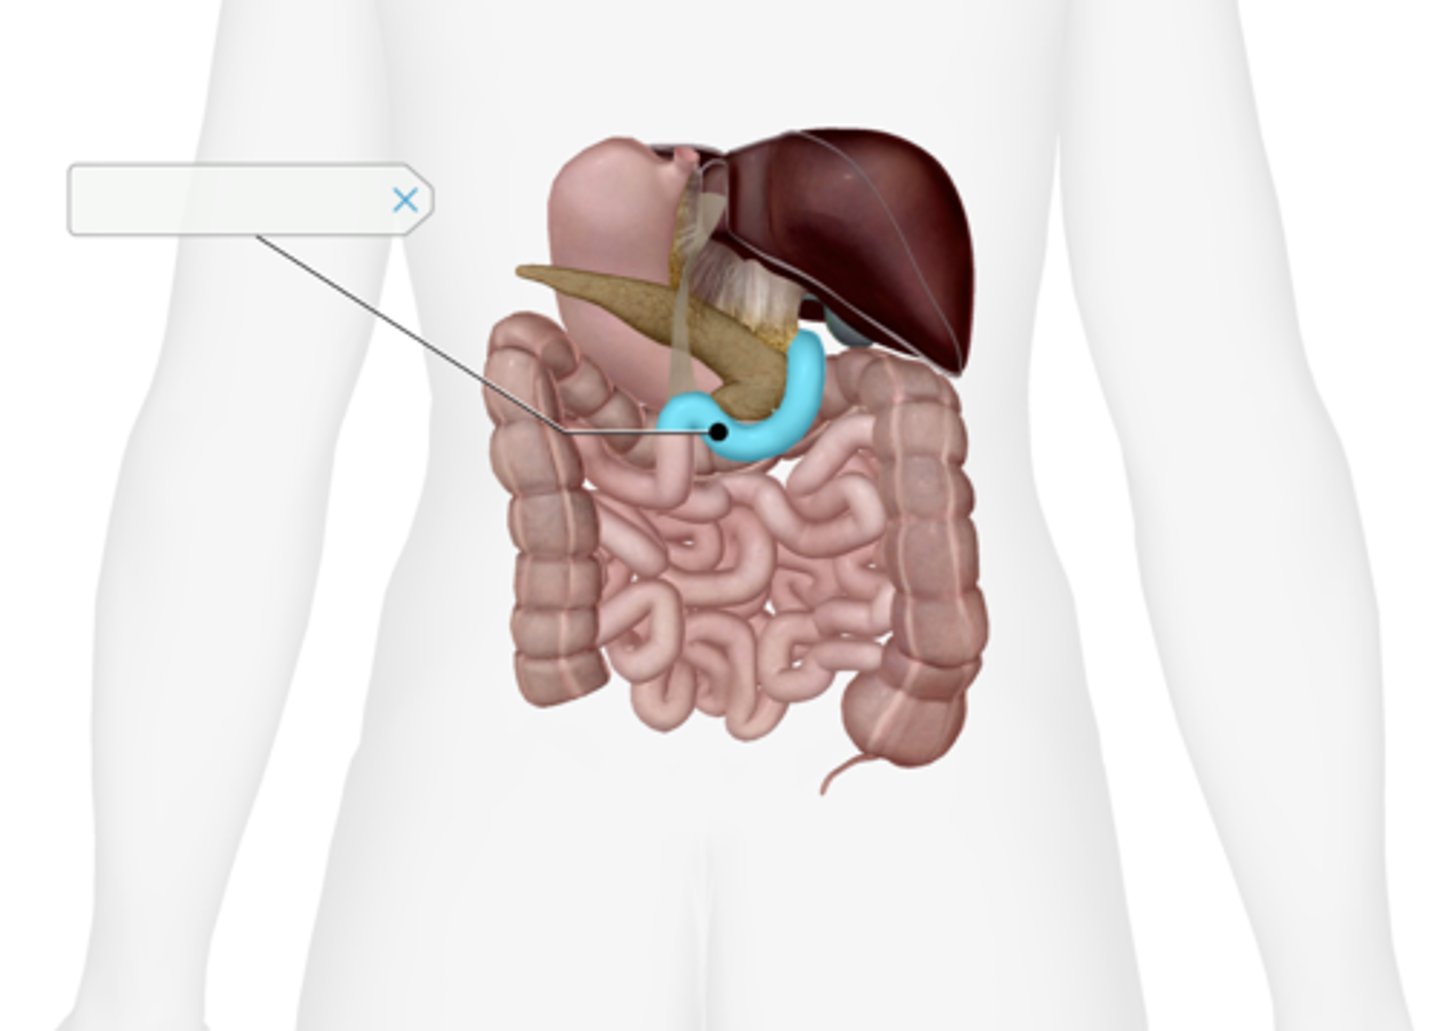

Gallbladder

Cystic duct

Common hepatic duct

Common bile duct

Pancreas

Main pancreatic duct (duct of Wirsung)

Accessory pancreatic duct (duct of Santorini)

Liver

Duodenum

Duodenal papilla